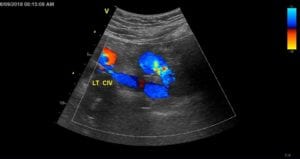

Authors: Tae An Choi ANP-BC, & Back Kim MD FACC. Heart Vein NYC, New York, New York Before (Right): 50 year-old male, a retail sales read more